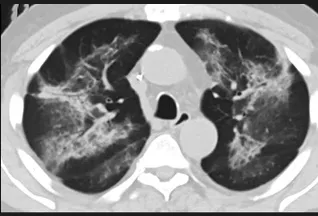

更值得注意的是,有之前应对过武汉新冠疫情的中国权威肺病专家,在查阅了60篇涉及美国“电子烟肺病”病例的研究论文,并对其中142位电子烟肺病患者的250张肺部影像图片、临床信息以及文献原文进行了仔细全面的研究后,发现这些病例中有16个更有可能是新冠肺炎的“疑诊患者”,有5个临床症状和治疗情况相对完整的患者,还被这些专家认定为了“中度可疑”。另外,这16个病例中有12个病例的发病时间,都在2020年以前。

新冠病毒是否来自美国?迄今为止最全面的线索来了

(这4张图,是专家怀疑被误诊为电子烟肺病的其中一个病例的肺片。专家表示,他们不是仅仅通过一张影片做判断的,而是通过这4张涵盖了这名病例肺部多天变化情况的影片进行的研判,认为该病例的病程进展跟新冠更为相似)